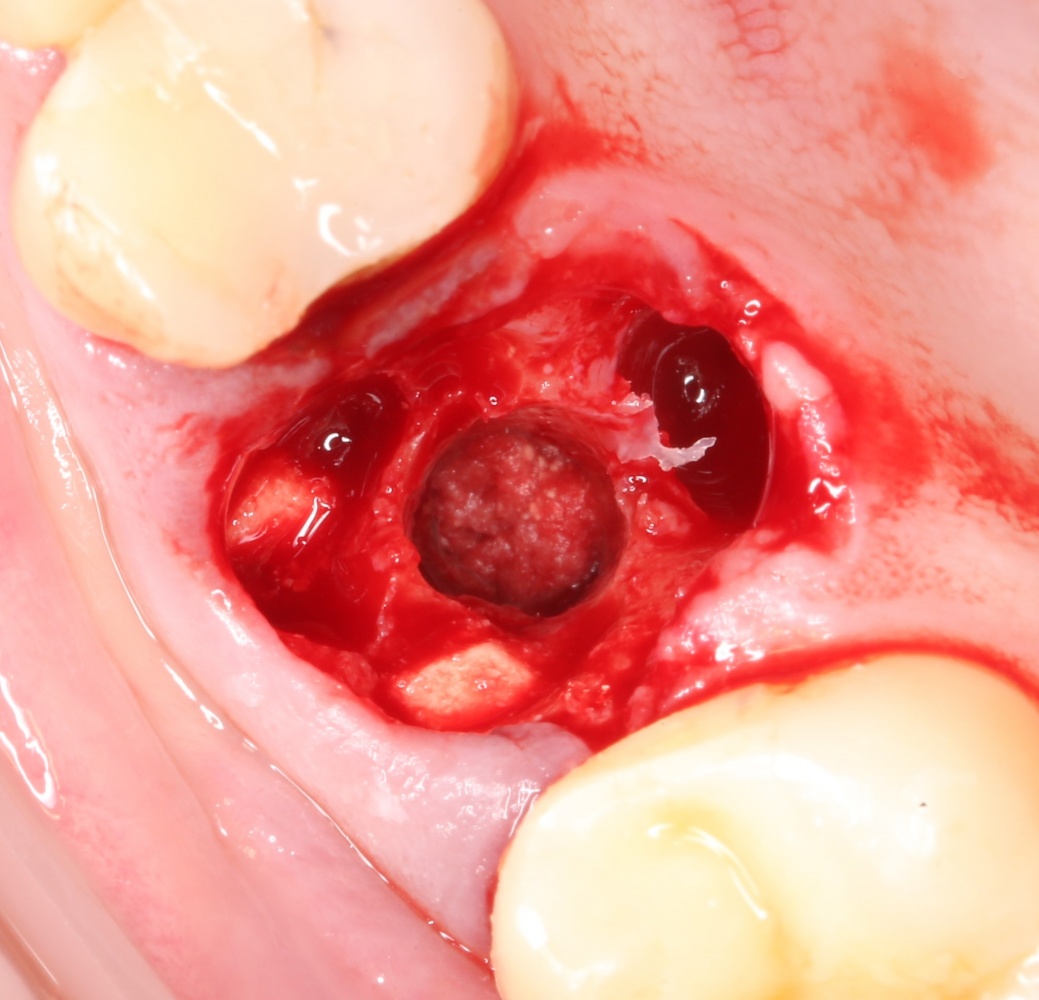

Синуслифтинг: что делать при перфорации слизистой оболочки гайморовой пазухи?